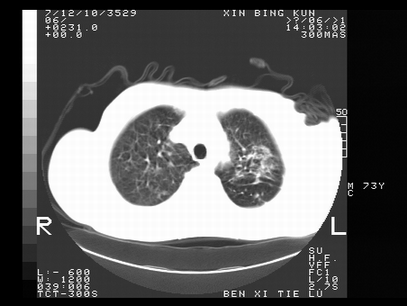

标题: CT10820:男,73岁,病史肺TB,现病史肺炎,直肠CA术后 [打印本页]

标题: CT10820:男,73岁,病史肺TB,现病史肺炎,直肠CA术后

1.两肺结核.2.两肺多发转移瘤.3右侧少量胸腔积液4.主动脉钙化.

双肺多发结节及条片状致密影,右侧少量胸腔积液。临床:直肠ca术后,肺tb病史。综合考虑:1 双肺转移!2 继发性肺结核合并感染!

此人病史较复杂,原有肺结核,直肠癌术后。肺部病灶形态亦呈多形性。因此,不可仅以一种病来解释肺部的病变。双肺多发的类圆形结节灶,结合病史还是首先考虑转移瘤,而双肺其余病灶还需结合化验室检查,结核或肺部感染在无其它检查资料的情况下不好排除。还是那句话----放射科医生不是开照像馆的,我们也是医生,看片一定要多结合临床及其它检查资料。要当一名合格的放射科医生,并不比当一名临床医生容易,我们可别把自已不当医生看。

两肺多发结节影,并见滋养动脉与其相连,考虑 两肺转移. 右侧胸腔积液考虑胸膜转移.

左肺上叶下叶背段,右肺中下叶见多发斑片状、条索状高密度影,兵变周围小结节影形成“树芽”样改变。 左肺上叶舌段近前胸壁处及右肺中叶内侧段见结节影。右侧胸膜腔内见液体密度区。纵隔内未见明确增大淋巴结。考虑左肺上叶舌段近前胸壁处及右肺中叶转移瘤可能性大。两肺继发型肺结核。右侧胸腔积液。

还有心包少量积液。